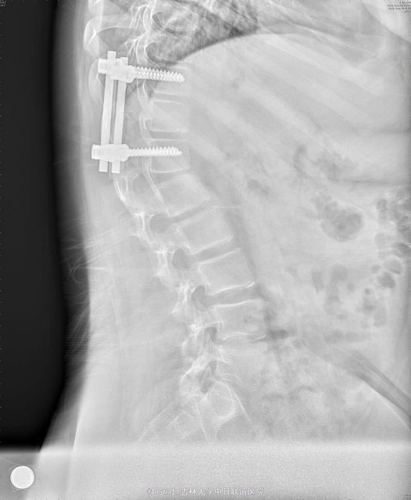

典型病例3:先天性脊柱侧凸

女/11/先天性脊柱侧后凸

病例分享 – - 先天性脊柱侧弯 t11半椎体畸形